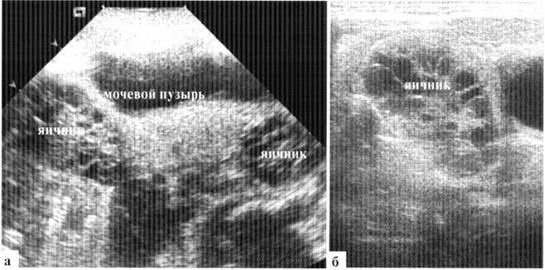

В норме визуализировать внутренние гениталии у новорожденной девочки удается не всегда, в основном из-за недостаточного наполнения мочевого пузыря ребенка на момент осмотра. В то же время, высокое расположение яичников у новорожденной делает возможным их визуализацию иногда и при опорожненном мочевом пузыре, даже из доступов в подвздошных областях. В некоторых случаях яичник на УЗИ определяется непосредственно под прямой мышцей живота. Строение внутренних гениталий новорожденной весьма вариабельно: яичники в норме могут иметь размеры как 6*Х мм с недифференцированными фолликулами, так и 35x25 мм с множественными фолликулами по 5—8 мм в диаметре (рис. 1.1).

Рис. 1.1. УЗ-варианты нормы яичников у новорожденных: а — яичники определяются is типичном месте при почти опорожненном мочевом пузыре; крупные (20x13 мм, мультифолликулярные); б — правый яичник мультифолликулярный, расположен высоко, около дна мочевого пузыря

Количество фолликулов в яичниках новорожденных может быть различным, достигая 10 и более в одном скане, при этом дальнейшее половое развитие девочек в течение первого года жизни протекает без особенностей. Такие мультифолликулярные яичники относительно часто наблюдаются у девочек, которые находятся на грудном вскармливании, что позволяет предположить роль материнского гормонального фона (рис. 1.2).

Рис. 1.2. Гиперстимулировнные яичники новорожденной: расположены высоко, рядом с боковой стенкой мочевого пузыря, по размером яичник сопоставим с мочевым пузырем